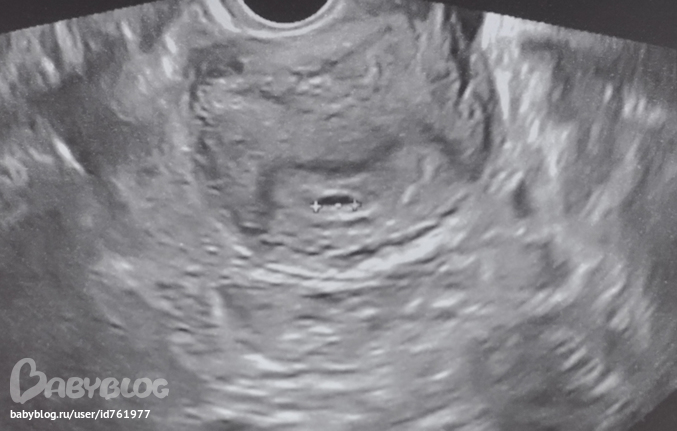

первое узи в 5 недель меня расстроило-плодное яйцо было на 3 недели и меня отказались ставить на учет-мол фиг его знает,может еще выкину.

а в 6 недель у нас уже есть сердебиение)))гора с плеч. КТР 5 мм,вот только плодное яйцо ненормально маленькое,но узистка сказала-так бывает.это не о чем не говорит